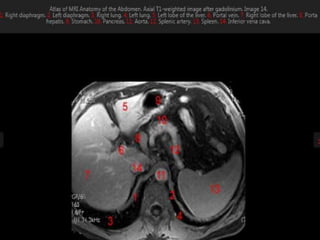

MRI anatomy images of the abdomen.

MRI anatomy imagesof the abdomen.